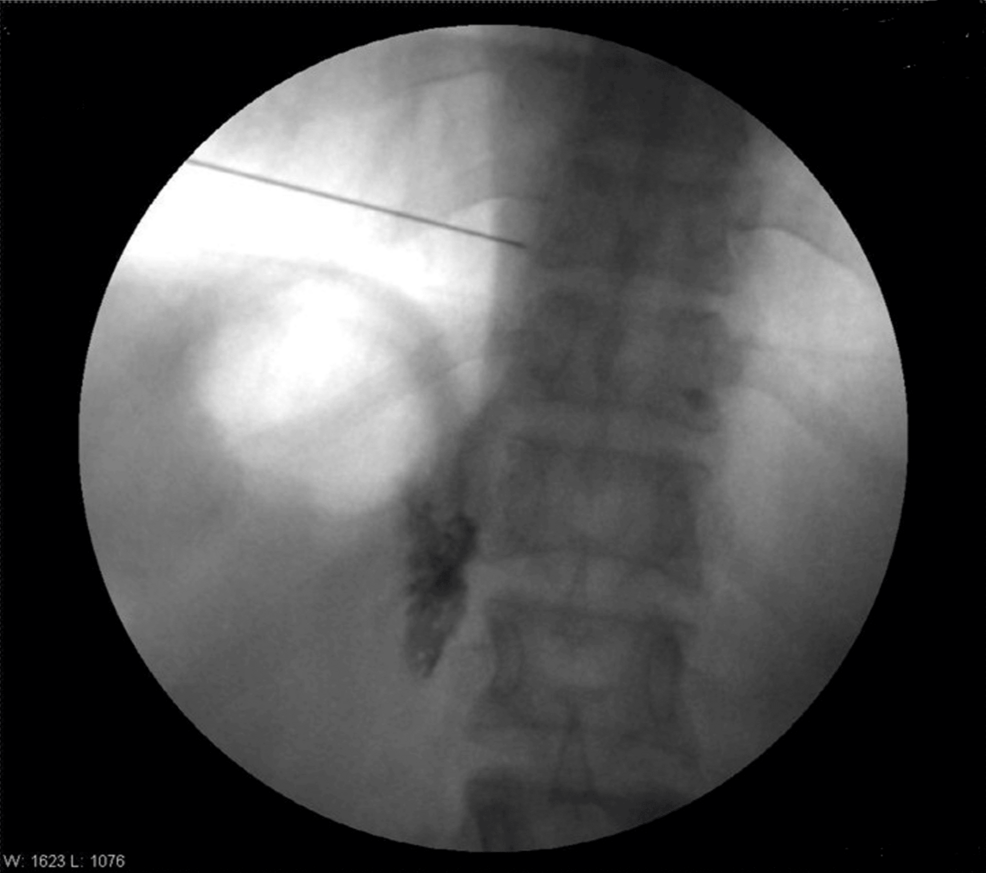

The patient was positioned prone. After painting and draping, the transverse process of T8 was located on the right side with the help of a C-arm. A Quincke needle (22 G) was inserted under fluoroscopic guidance to reach the transverse process of T8. The needle tip was advanced caudally along the transverse process until a loss of resistance was felt. The needle’s position was confirmed via fluoroscopy by injecting iohexol 300 radiocontrast dye, with images obtained in both anteroposterior and lateral views (Figures 1–4).

Four milliliters of levobupivacaine 0.5% were administered. Similar steps were performed for the T10 and T12 vertebrae. Sensory levels were assessed using hot and cold glass test tubes along the mid-axillary line. Motor blockade was evaluated using Snider’s match-blowing test, where the patient was asked to blow out a match held 15 cm from the mouth. Vitals after five minutes were HR of 90/min, BP of 100/68 mmHg, SpO2 of 98%, and RR of 14/min.